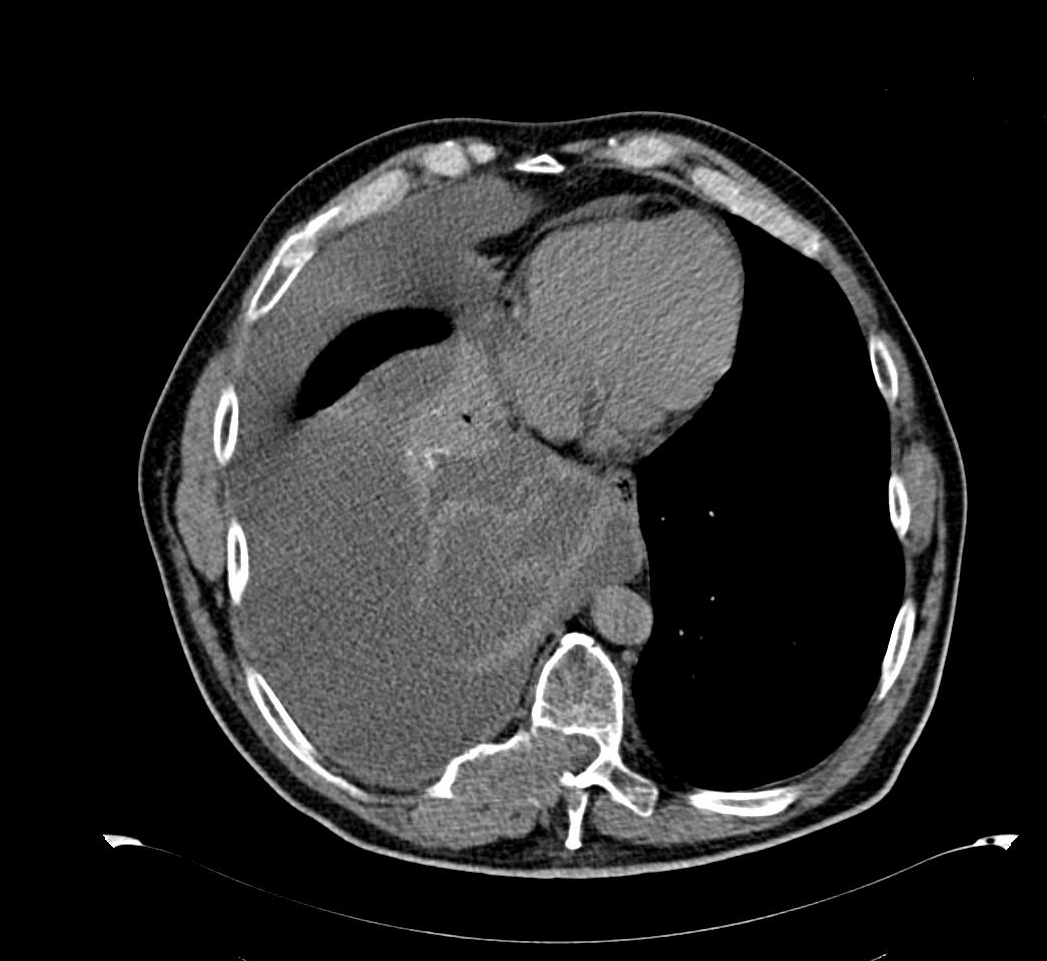

Ante sospecha de carcinoma renal con derrame pleural paraneoplásico remitimos a urgencias para ingreso y estudio. En 48 horas se llega al diagnostico final de carcinoma de células claras renal estadio IV con afectación pulmonar, pleural, ganglionar y ósea grupo pronóstico intermedio.Tratamiento y planes de actuación